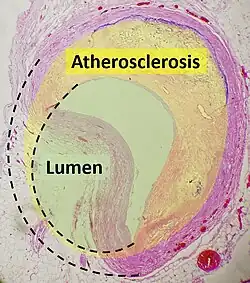

Coronary occlusion is caused by the buildup of fats, cholesterol and other substances in and on the walls of the hearts arteries.[6] As plaque builds up, the arteries narrow.[7] Plaque often starts building up during childhood and is heavily influenced by genetics, but also lifestyle and high blood cholesterol.[7] This condition is referred to as atherosclerosis.[6] The buildup on the walls of the hearts arteries is referred to as plaque. Plaque causes arteries to narrow and block blood flow.[6]

Coronary occlusion is caused by plaque inside of the blood vessels that direct oxygen rich blood to the heart.[8] Plaque is caused by fatty deposits and scar tissue that cling to the walls of coronary arteries.[9] The development of plaque takes years and leads to stenosis of the coronary arteries and progressively reduces blood flow.[8] Due to the slower development of this condition, the body will adapt and create small blood vessels that circumvent the blockage.[8] The small blood vessels form a natural bypass of the blockage, but often do not supply enough blood to meet an increased demand when stressors are applied like exercise.[8]

When a plaque has a greater than 50% diameter stenosis, the reduced blood flow through the coronary artery during exertion may lead to angina.[10] Acute coronary events occur when a thrombus forms due to disruption of a plaque.[10] In acute heart attack, occlusion is greater than in unstable angina, where arterial occlusion is not full blockage. Downstream embolism of thrombus may also produce microinfarcts.[10]